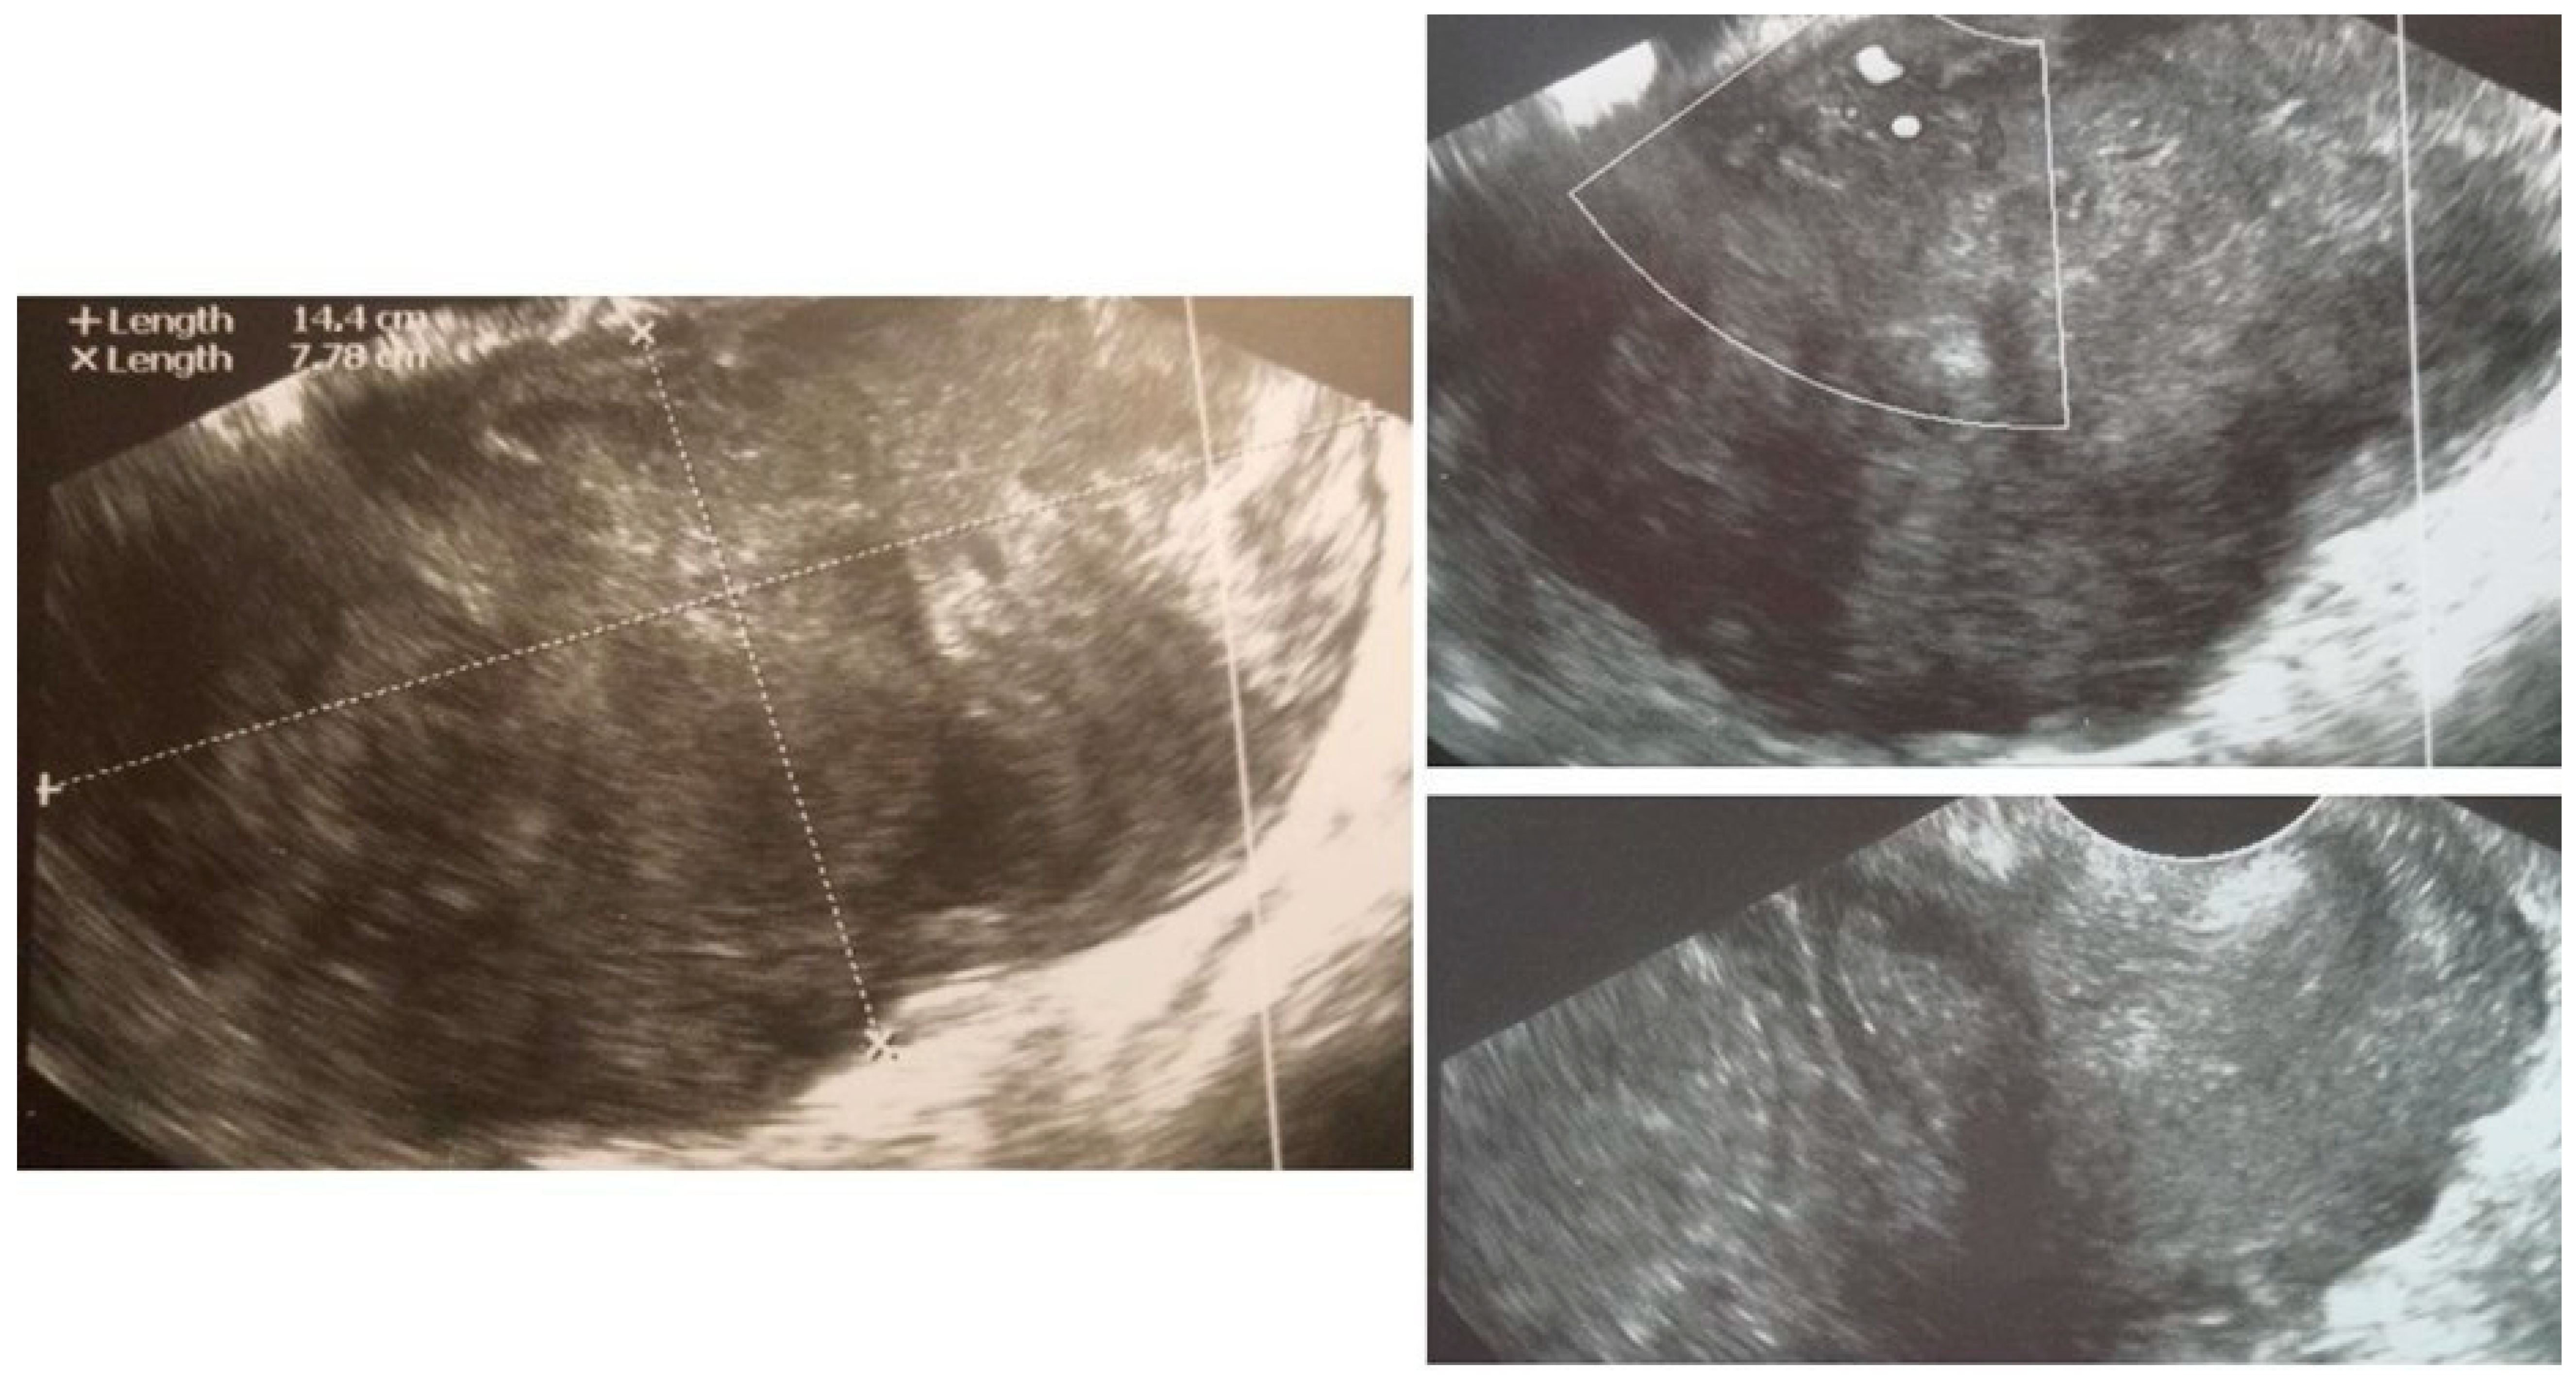

| 5 (50) | Atypical uterine lesion (metastatic adenocarcinoma G3 in inguinal lymph node) | Figure A5 | Yes | No | Leiomyoma (UG-TUC core needle biopsy) | No | Uterus / tumor not resected because primary urological carcinoma was diagnosed | Yes | Yes |